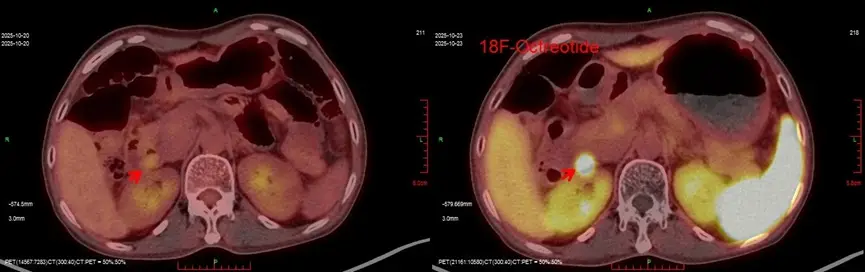

Sau khi loại trừ các bệnh lý nhiễm trùng và viêm tụy, các bác sĩ chuyên khoa đã xác định bệnh nhân có triệu chứng tiêu chảy tiết dịch. Đây là một dạng tiêu chảy hiếm gặp, thường liên quan đến u thần kinh nội tiết. Kết quả xét nghiệm máu cho thấy chỉ số chromogranin A tăng cao gấp 12 lần so với mức bình thường, điều này càng củng cố nghi ngờ lâm sàng về tình trạng của bệnh nhân.

Hình ảnh siêu âm.